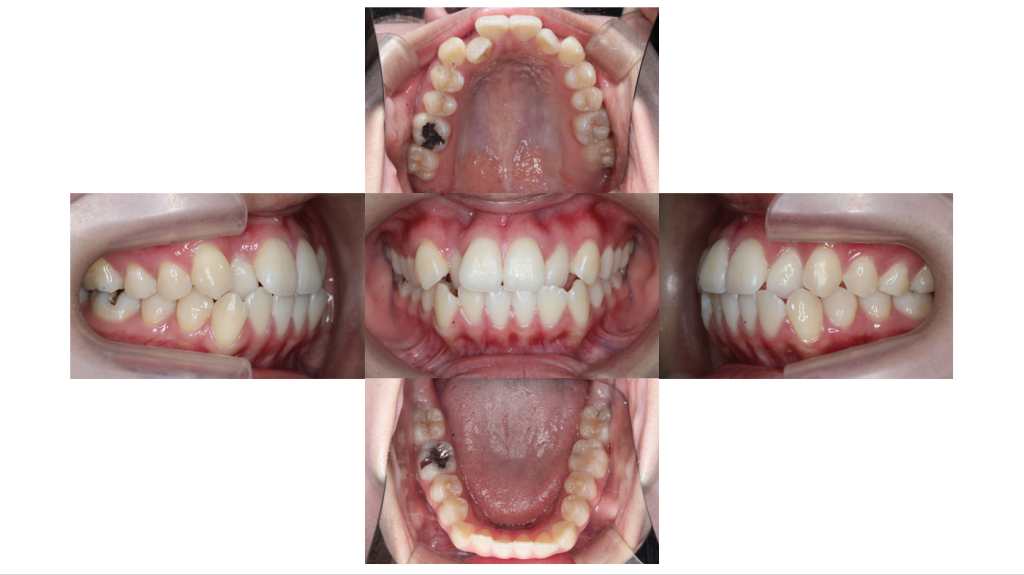

初診

叢生・裏側矯正の症例装置装着前の口腔内です。